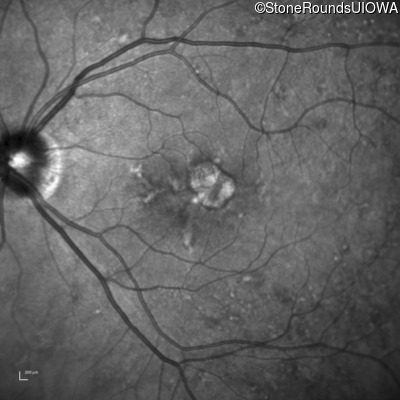

Fundus Photography - Right - 20/20 +2

Exemplar